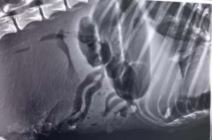

Ona je potom odvela psa kod veterinara u Ivanjicu. Rendgen je pokazao da je ženka psa upucana sa šest metaka.

"Veterinar u Ivanjici joj se borio za život, izvlačio joj je krv i vodu iz pluća, kada je počela da se guši. Jaukala je sve vreme, a kada je urađen rendgen, ispostavilo se da je neko pucao u nju. Imala je šest metaka, od toga dva u kičmi, koja veterinar nije smeo da izvadi, s obzirom na položaj", dodala je Svetlana.

Pogledajte fotografije ranjenog psa kod Sjenice